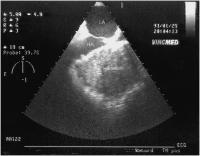

Rete chiari

Abbildung 2: Rete chiari (TEE, Längsschnitt)